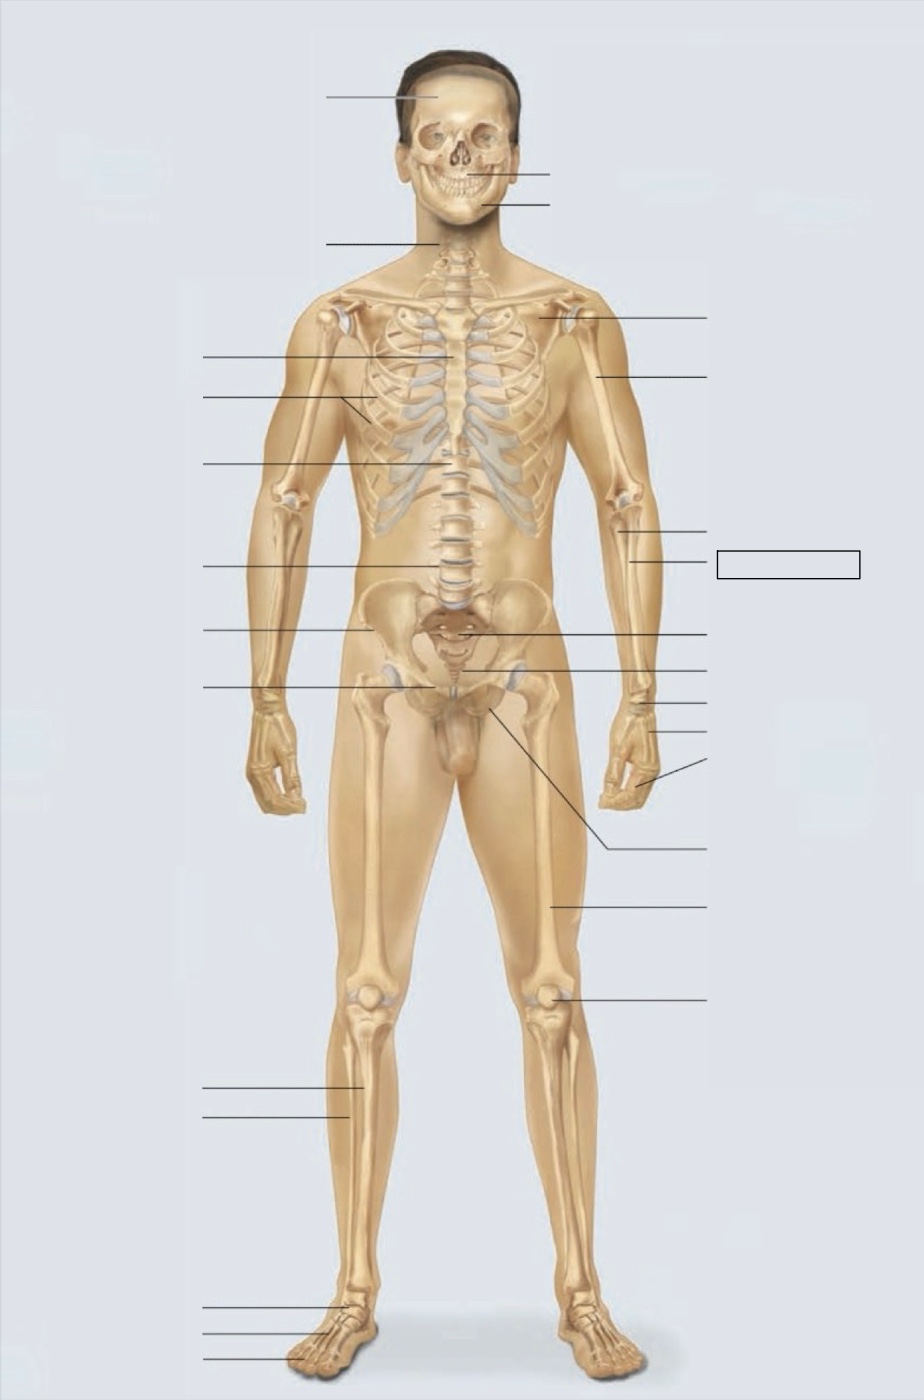

maxilla

mandible

scapula

humerus

ulna

radius

sacrum

coccyx

carpals

metacarpals

phalanges

ischium

femur

patella

phalanges

metatarsals

tarsals

fibula

tibia

pubis

ilium

lumbar vertebrae (L4)

thoracic vertebrae (T11)

ribs

sternum

cervical vertebrae

skull